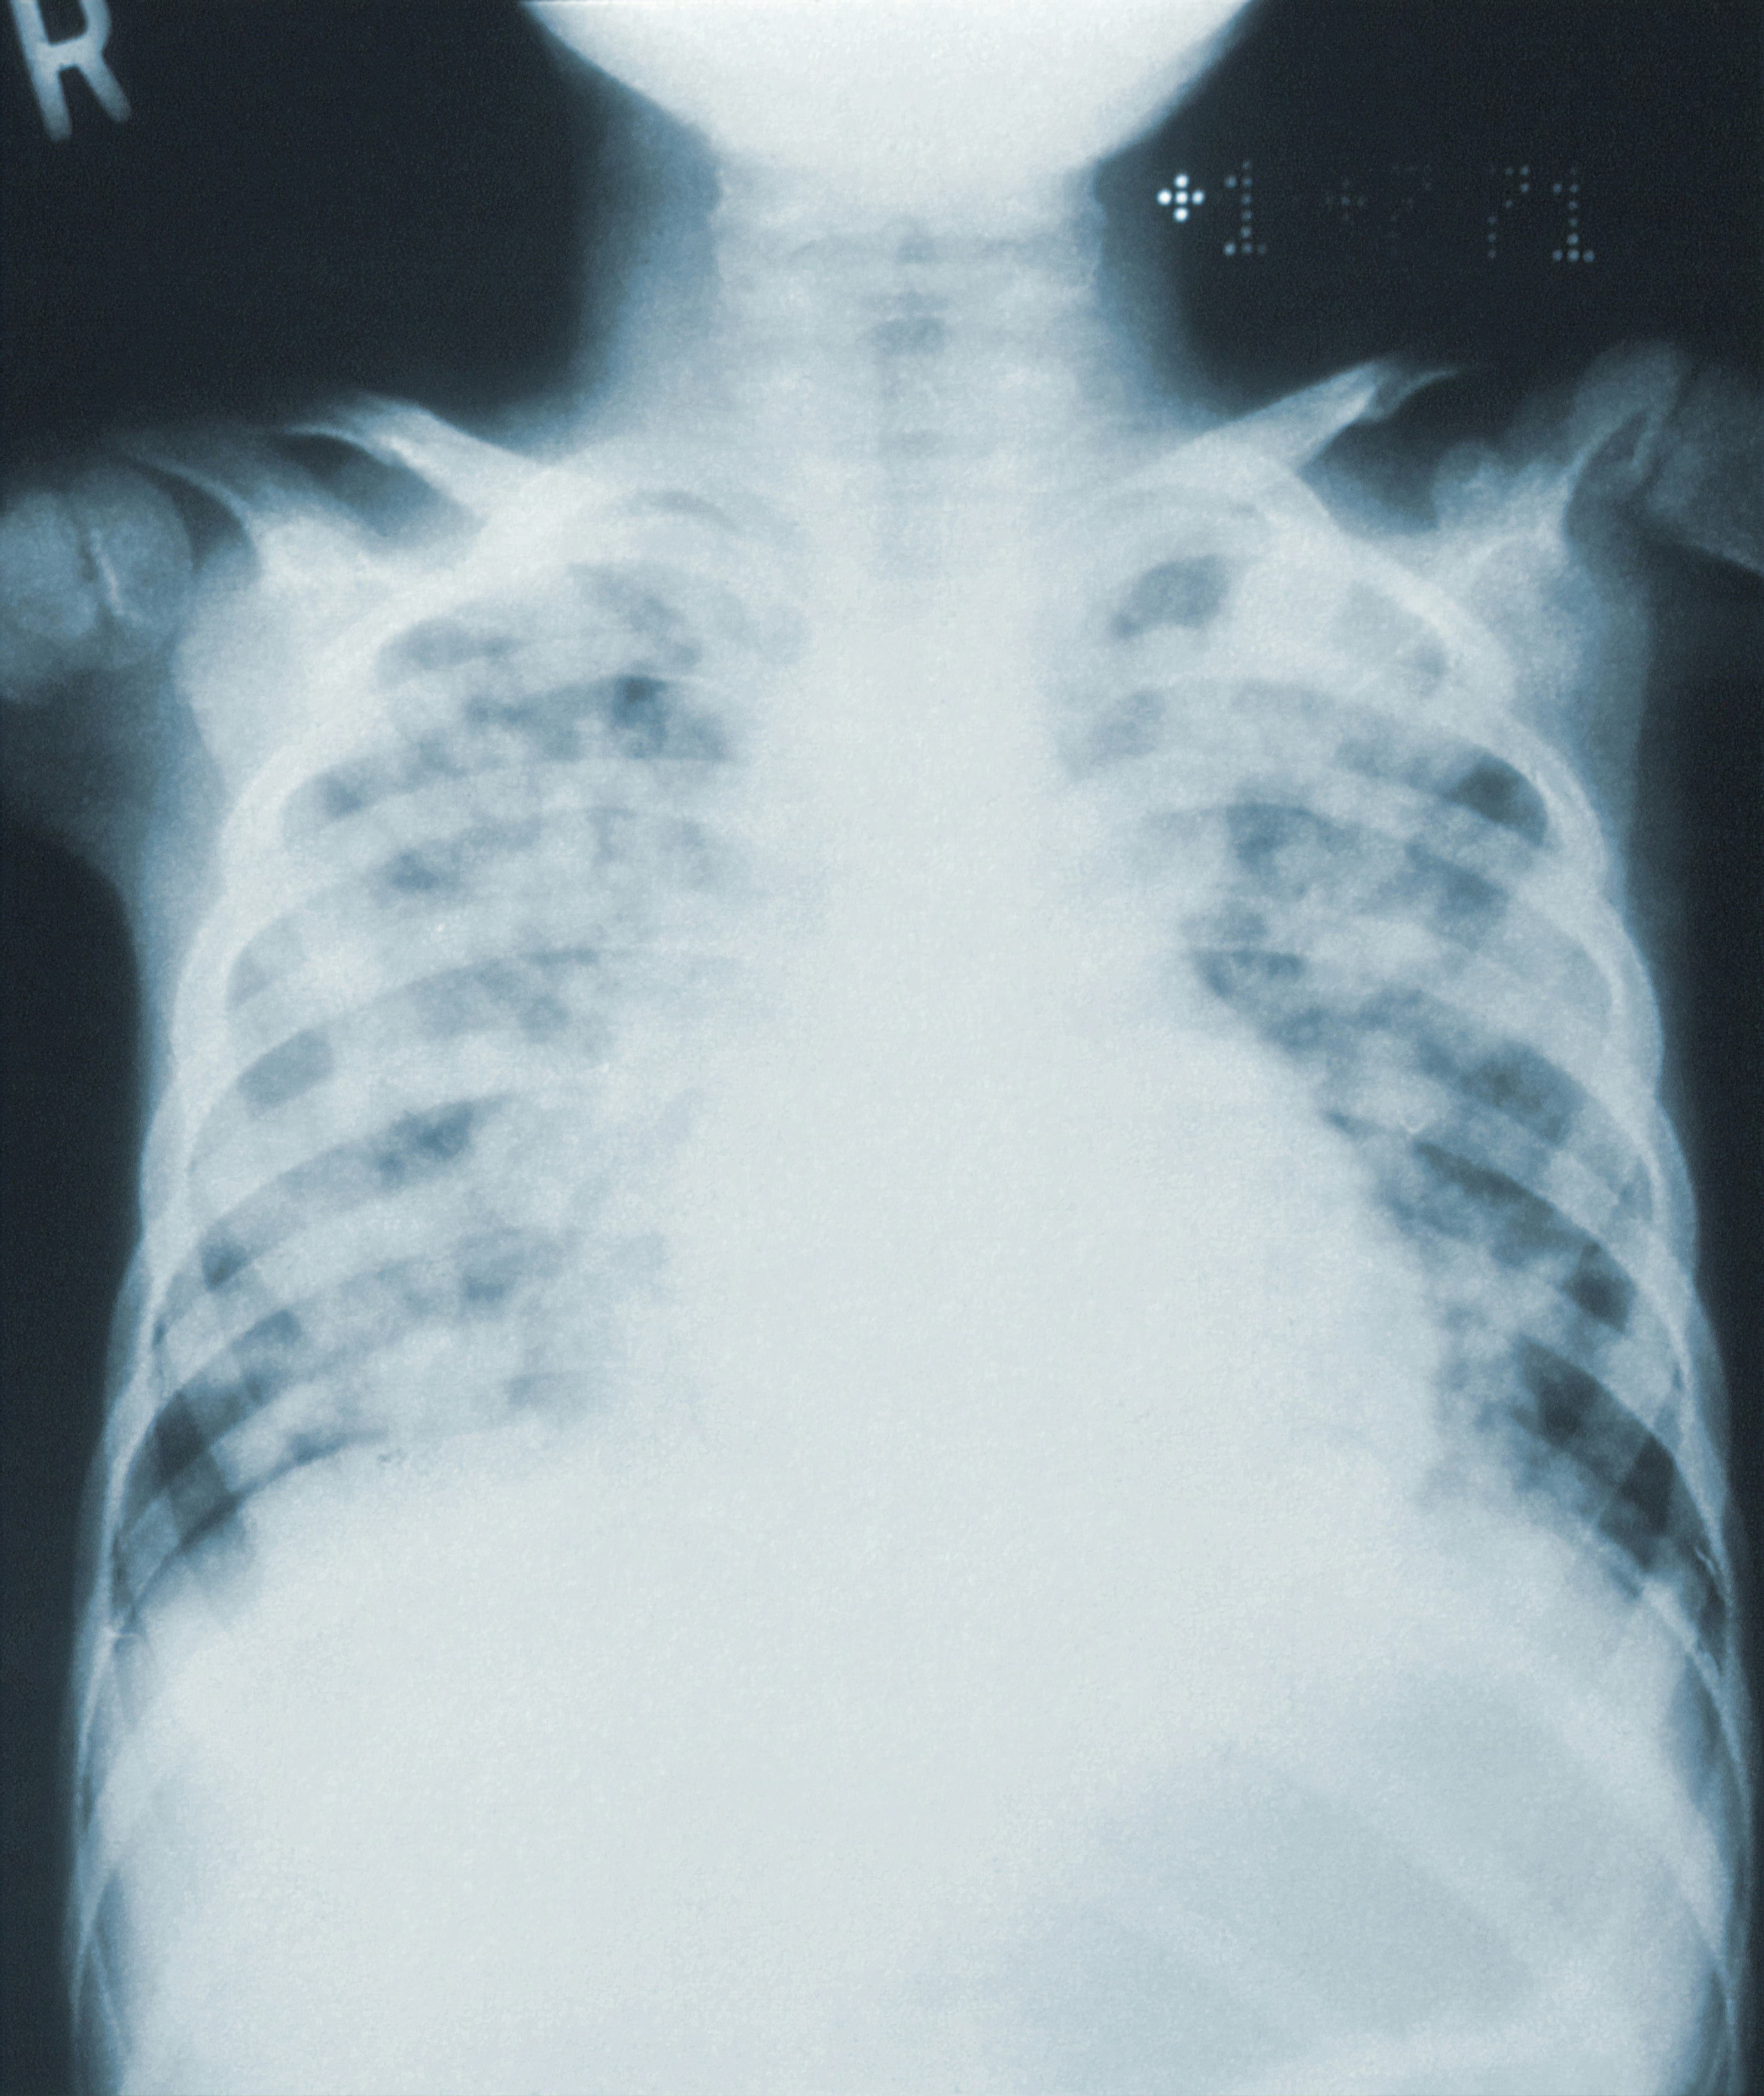

La computer vision par TDM pour identifier les patients inconnus

La computer vision a un bon potentiel pour identifier des personnes inconnues explorées en situation d’urgence. Une étude publiée dans la Revue European Radiology évalue l’efficacité du MIP par TDM thoracique pour que la computer vision puisse identifier des patients. Cette méthode est applicable à...